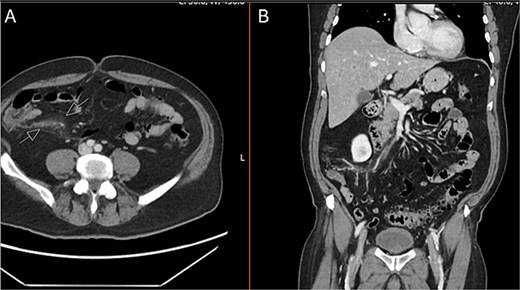

The patient was admitted to the surgery service for resuscitation and close monitoring. Given his prior thrombotic event, the patient was started on a continuous heparin infusion, anti-Xa goal 0.3–0.7. The patient received 2 L of intravenous fluids as well as a continuous fluid infusion of lactated ringers at 100 cc/hr. The surgery team performed serial abdominal exams which remained stable. Additionally, he was started on prophylactic ceftriaxone and metronidazole. A CTA abdomen and pelvis was subsequently performed, which revealed occlusion of the ileocolic vein with perivenous inflammatory change, consistent with mesenteric thrombophlebitis (Fig. 2). The celiac trunk, superior mesenteric artery, renal arteries and inferior mesenteric artery were all patent. Venous phase imaging showed patent portal vein and patent main superior mesenteric vein. On hospital day (HD) 1, the patient’s lactic acidosis cleared. A GI PCR was obtained which was positive for enteropathogenic E. coli (EPEC). Hematology and Oncology was consulted and recommended continued therapeutic anticoagulation and outpatient oral anticoagulation. The patient had a short period of respiratory distress on HD 2, attributed to be secondary to volume overload, and responded appropriately to diuretics. On HD 3, the patient’s leukocytosis resolved, and he was slowly advanced to a regular diet. On HD 4, the patient was discharged on remaining course of amoxicillin-clavulanic acid (Augmentin). After discharge, the patient’s blood cultures returned positive for Fusobacterium nucleatum and his Augmentin course was extended for an additional seven days.

CTA abdomen and pelvis venous phase. A) Axial and B) coronal series revealing filling defect within the ileocolic vein with surrounding inflammatory changes, consistent with mesenteric thrombophlebitis of the ileocolic vein.